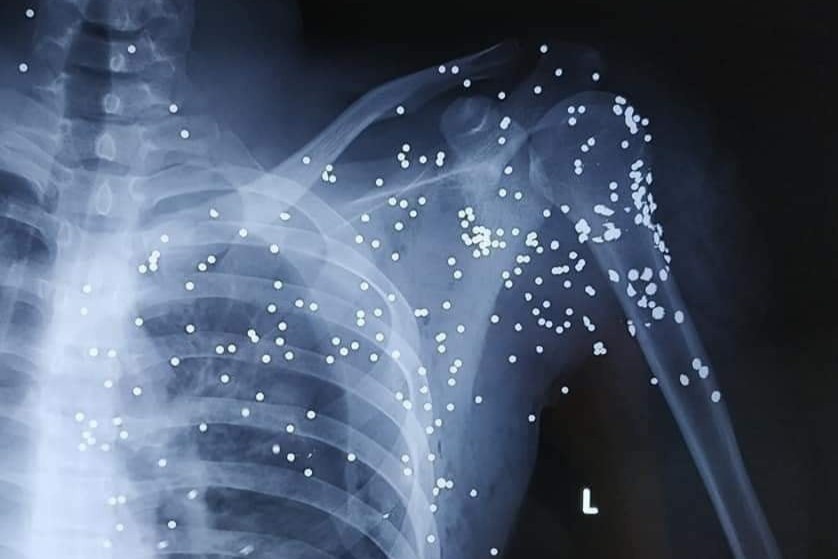

Bác sĩ đếm được trên người Hoàng có khoảng 60-70 vết đạn, chưa tính tới những viên đạn chồng lên nhau, bị che khuất mà hình ảnh chụp X-quang không thể thấy được.

Anh Hải cho biết các bác sĩ đếm được trên người Hoàng có khoảng 60-70 vết đạn, chưa tính tới những vết đạn chồng lên nhau, bị che khuất mà hình ảnh chụp X-quang không thể thấy được.

Anh Hải cho biết bác sĩ đếm được khoảng 60-70 vết đạn trên người em trai mình. Ảnh: Gia đình cung cấp.